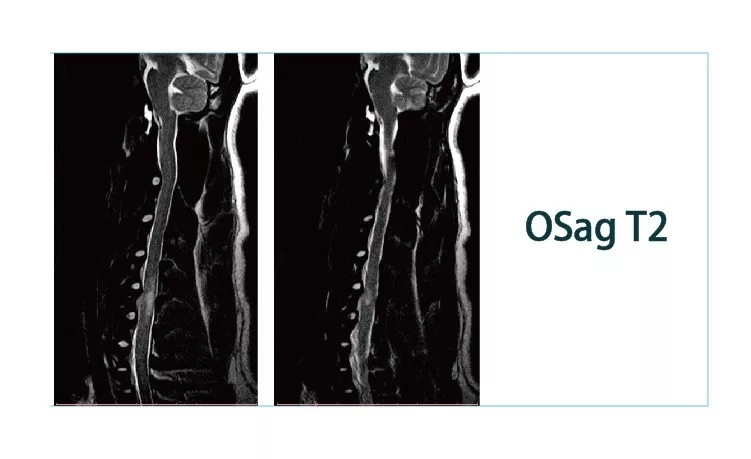

640.webp (4).jpg